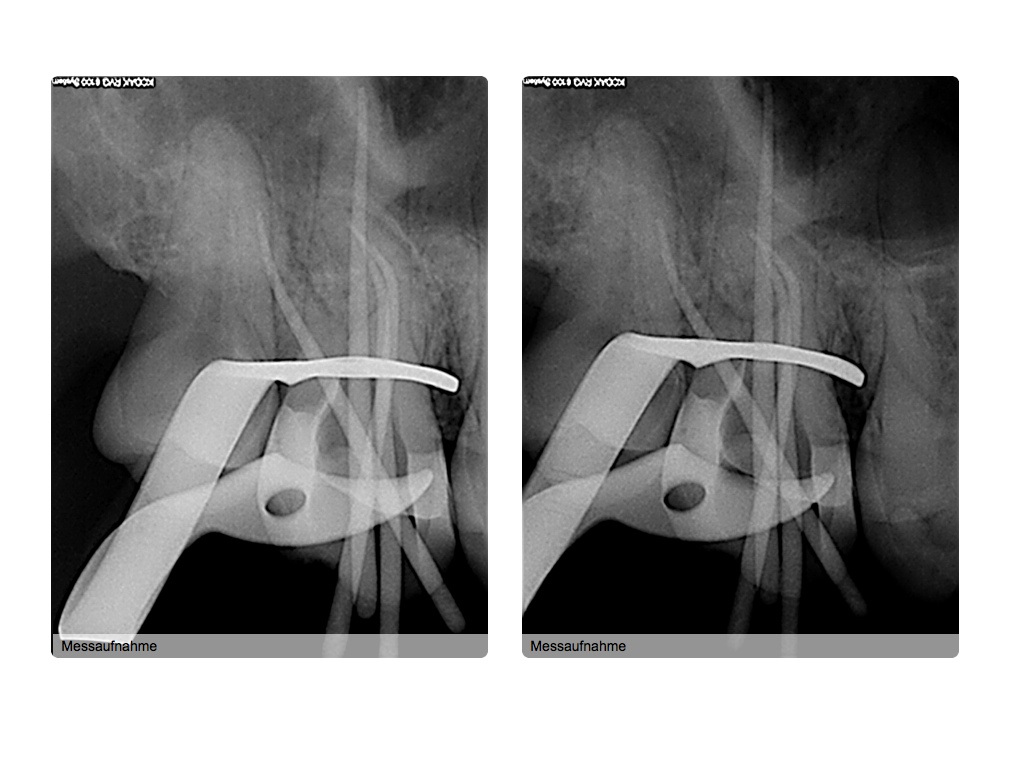

Was würden Sie machen, wenn es Ihr Zahn wäre?